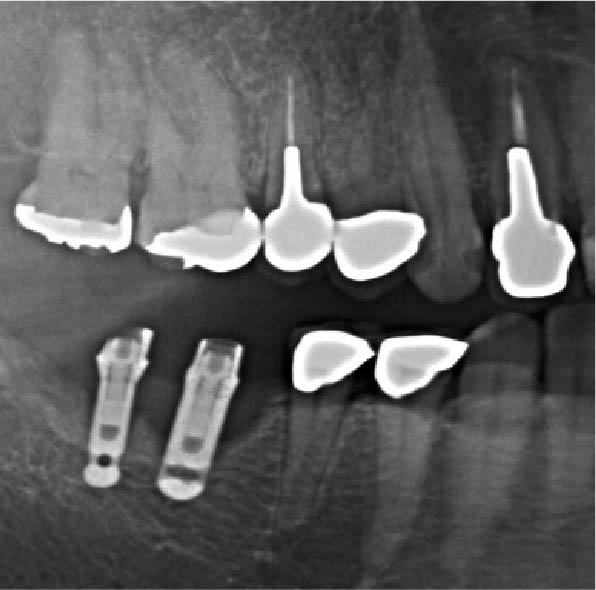

インプラントの周りを専用の器具(プローべ)で軽くなぞるように触ってみて歯茎から出血するか調べる

出血すれば炎症が起きている証拠

出血が治まってなければ、被せ物を外して汚れをとる

天然の歯は抜いて歯石などの汚れを取って、また植える。なんてことは出来ないので、この点ではインプラントは有利

インプラントと被せ物はネジで留めてあるので、外して被せ物の周りの汚れを洗浄できます。